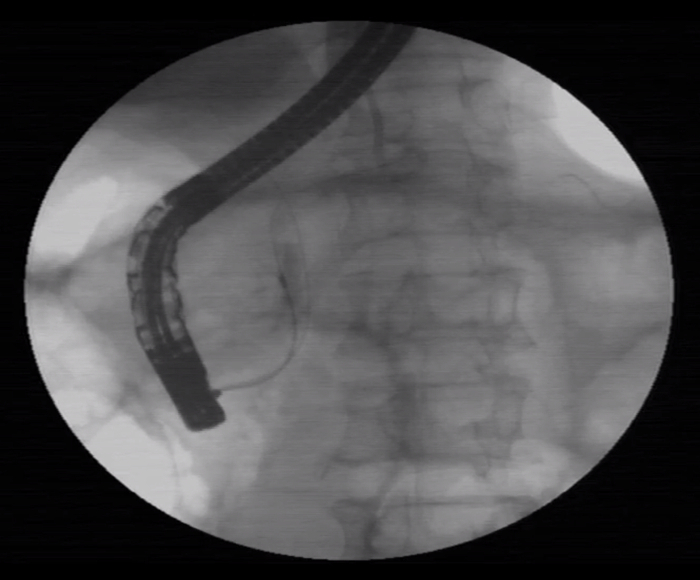

患者男,65岁。于十二指肠内侧找见主乳头,乳头呈鼻型,开口呈绒毛样。胆管狭窄导致反复超选导丝无法进入,后使用一次性粘膜切开刀,沿胆管方向行预切开,再次插管导丝进入胆管,注入少量造影剂,胆管显彰。

患者于三月后更换胆管支架,十二指肠镜应用操作如图所示: